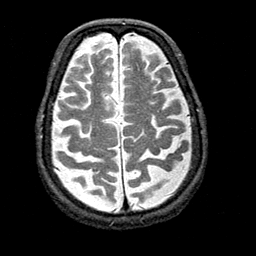

Alzheimer's disease MR T2-weighted -- Slice #36

[Home][Help][Clinical][Tour 1][Tour 2] Slice 36